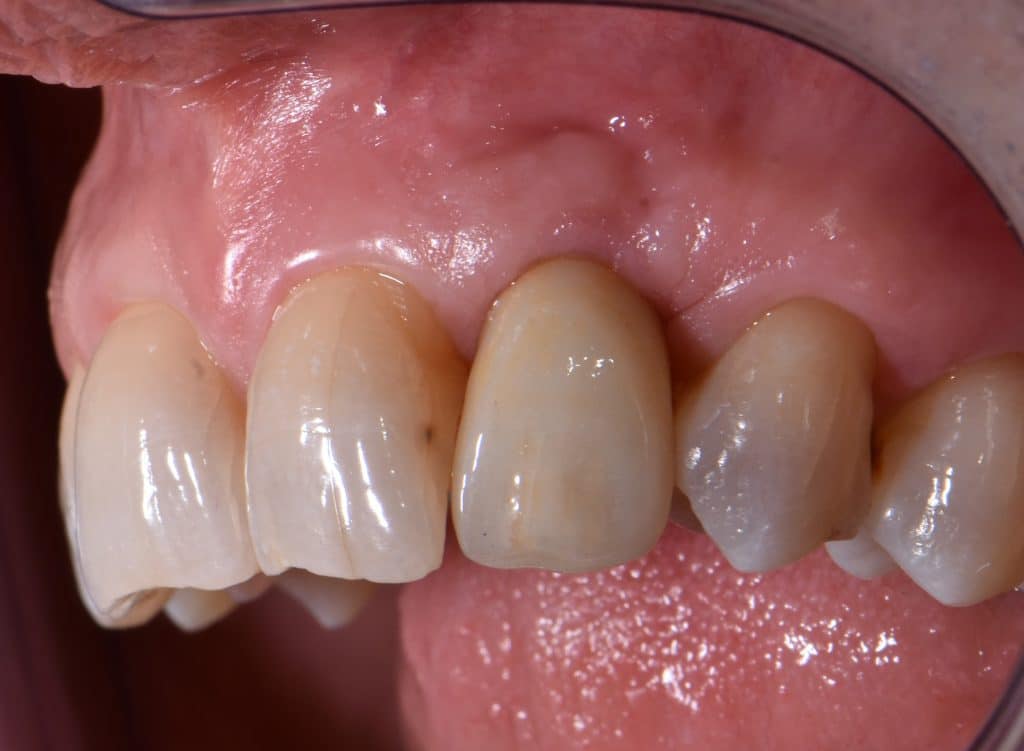

La pz N.G. di anni 52 (ASA 1) viene visitata nel mese di settembre 2017 per la mobilità ed inestetismo dell’elemento protesico 22, (foto iniziali sequenza 1) si evidenzia una frattura parziale della radice, si decide per l’estrazione ( foto sequenza 2) e sostituzione dell’elemento con un restauro implanto-protesico. Purtroppo la scarsa quota ossea apicale all’alveolo post-estrattivo (foto 2 rx) e l’alta valenza estetica dell’elemento ci rende cauti e si programma una socket preservation post estrattiva con l’ausilio delle membrane di prf (foto prf e socket sequenza 3 e 4). Durente i 5 mesi di guarigione la pz porta una protesi parziale mobile (foto 5,2) , a guarigione del sito post estrattivo si evidenzia una buona conservazione dei volumi osseo-gengivali,(foto guarigione sequenza 6) se pur presente una recessione distale all’elemnto 21.Nel mese di febbraio 2018 si procede all’inserimento di un impianto max-stability 3,75x12mm disegnando un lembo anticipato palatino per consentire un aumento dei tessuti vestibolari suturando con tecnica rool flap e trasformando l’elemento parziale mobile in una corona singola a carico immediato sul moncone temporameo applicando i concetti protesici bopt , (foto impianto moncone protesi provvisoria sequenza foto 7-8-9). Durante il periodo di maturazione dei tessuti molli vengono apportate opportune modifiche ai profili del provvisorio al fine di dare maggior spazio al tessuto gengivale, ( fotosequenza 10).Dopo circa 2 mesi dal protesizzazione provvisoria si è proceduto alla realizzazione del manufatto protesico con tecnica chair side sirona con l’ausilio del t-base (foto sequenza 11-12-13), realizzando in una sola seduta una corona in disilicato, ottenendo un risultato più che soddisfacente (Foto 14). Nel controllo a 3 mesi dal carico definitivo si apprezza la perfetta conservazione dei livelli ossei e gengivali. (foto sequenza 15).concludo con un follow up a 18 . Tengo a sottolineare che un caso come questo è stato conducibile con buoni risultati solo grazie alla piena fiducia della pz e alla sua massima motivazione e collaborazione. Ad oggi la pz sorride soddisfatta del risultato. E questo rappresenta la massima ricompensa di chi dedica tutto se stesso alla professione.